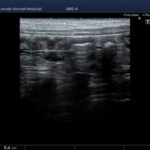

頻繁に嘔吐・下痢をするワンちゃんの精密検査依頼で内視鏡検査のご紹介がありました。内視鏡検査で上部・下部消化管を検査し、粘膜を採取し病理組織検査に出しました。結果は「胃:らせん菌感染を伴う慢性胃炎(中程度)/結腸:慢性腸炎(軽度)」とのことでした。その後かかりつけの先生のところ […]